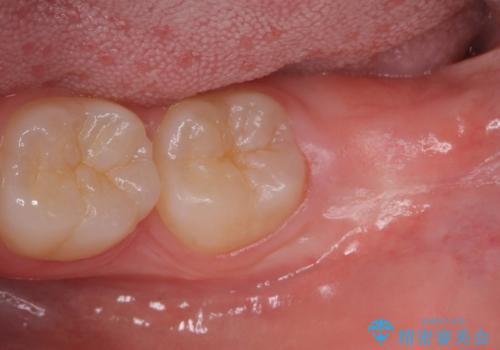

親知らずは入院せずとも通院で片側上下同時に抜くことが可能です。

手前の歯の虫歯リスクを下げるためにも、骨から出てきた親知らずは抜くことをお勧めします。

また術後丁寧に縫合をすることで治癒後の歯茎の状態もきれいにすることができます。